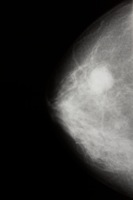

mammogramBorstkankerscreening is één van de belangrijke elementen in het federaal kankerplan van minister van Sociale Zaken en Volksgezondheid, Laurette Onkelinx. De eerste voorstellen die de Technisch Geneeskundige Raad (TGR) hierover op tafel legde, druisten lijnrecht in tegen de visie van Domus Medica over wat een goede screening moet zijn. De taalgrens bleek hier een zorggrens te zijn. ‘In Franstalig België zweert men bij een senologisch bilan’, legt Bart Garmyn uit. ‘In plaats van gebruik te maken van een kwaliteitsvolle screeningsmammografie worden veel vrouwen er aan een diagnostisch onderzoek (mammografie plus echografie) onderworpen. Vanuit wetenschappelijk oogpunt is er geen evidentie om deze manier van werken te ondersteunen. Een conclusie waar ook het federaal Kenniscentrum (KCE) in een recent rapport toe kwam.’ Het ‘systematisch’ uitvoeren van een echografie brengt uiteraard een stijging van de kosten met zich mee en levert bovendien geen kwaliteitswinst op. ‘Resultaat is een groot aantal nutteloze vervolgonderzoeken, overdiagnose en overbehandeling. De vele vals-positieven leiden tot meer invasief onderzoek en tot ‘meer borstkankers’. Diegenen die echt zorg nodig hebben, zullen echter langer op de wachtlijst moeten staan en ontberen zo noodzakelijke zorg.’